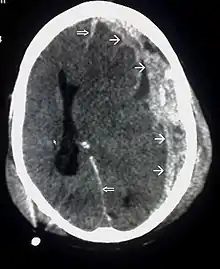

واحدة من أنواع الإصابات البؤرية هي التهتك الدماغي، وتحدث عندما يتم قطع الأنسجة أو تمزقها.[30] وهذا التمزق شائع في القشرة الجبهية الحجاجية على وجه الخصوص، بسبب النتوءات العظمية الموجودة على حافة الجمجمة الداخلية فوق العينين.[24] وهناك إصابة مماثلة هي الرضة الدماغية (كدمات في أنسجة المخ)، حيث يمتزج الدم بين الأنسجة.[15] في المقابل، لا يختلط الدم في حالة النزف داخل القحف مع الأنسجة.[30]

الأورام الدموية، هي أيضًا إصابات بؤرية، وهي عبارة عن تجمعات من الدم في أو حول الدماغ يمكن أن تنتج عن النزف.[3] النزيف المخي هو آفة داخل المحور نفسه حيث تنزف أنسجة المخ نفسها. بينما تشمل الآفات خارج المحور الورم الدموي فوق الجافية، الورم الدموي تحت الجافية، ونزف تحت العنكبوتية، والنزيف داخل البطين.[31] ينطوي الورم الدموي فوق الجافية على نزيف في المنطقة بين الجمجمة والأم الجافية، الغشاء الخارجي من الأغشية الثلاثة المحيطة الدماغ.[3] وفي الورم الدموي تحت الجافية، يحدث النزيف بين الأم الجافية والأم العنكبوتية.[15] بينما ينطوي نزف تحت العنكبوتية على النزيف في الفضاء بين الغشاء الأم العنكبوتية والأم الحنون.[15] ويحدث النزيف داخل البطين عندما يكون هناك نزيف في الجهاز البطيني.[31]